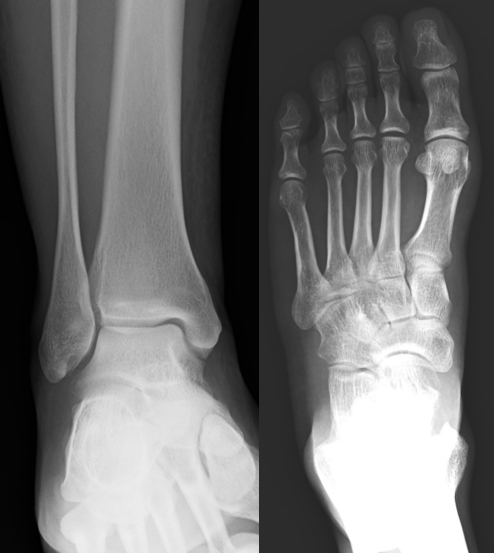

図1.正常な足関節正面(左)と足部(右)のX線画像。